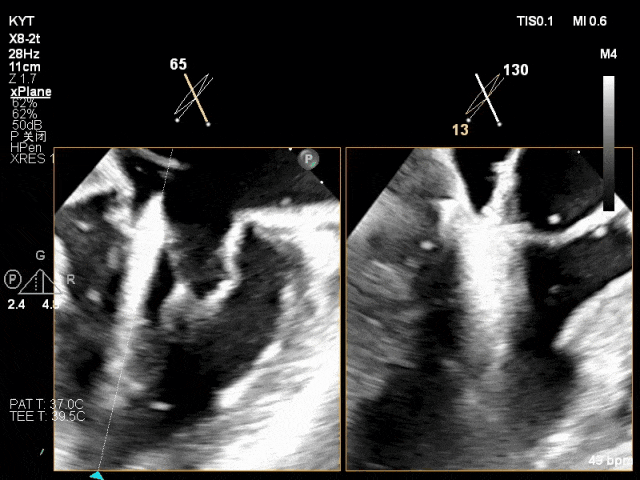

TEE X-plane示二尖瓣内交界区脱垂

TEE X-plane with color Doppler